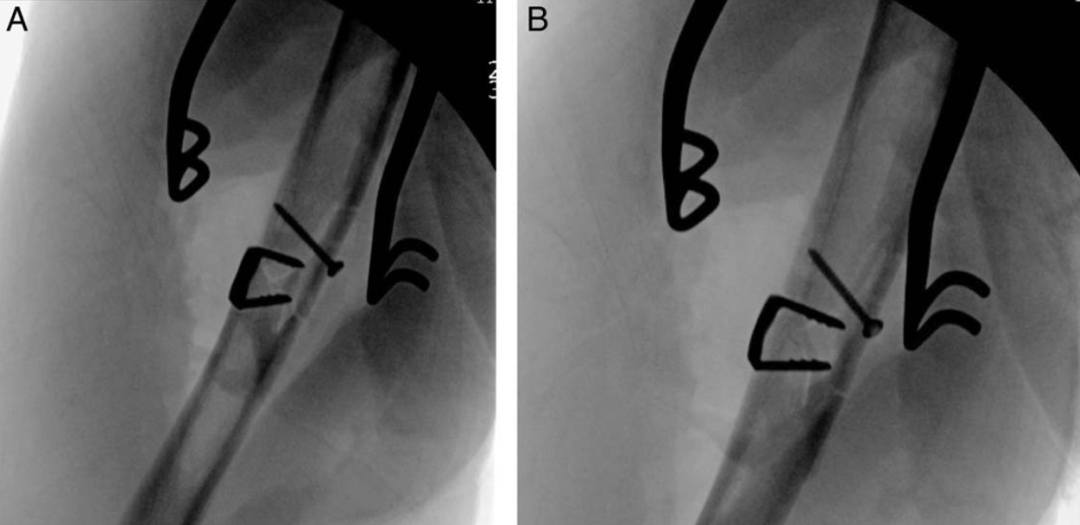

然而,由于其操作简便,并具有良好的固定强度,在骨折内固定中,也有学者单独/辅助使用或临时固定使用,从治疗出发获得了良好的临床效果。如肱骨干骨折复位后的临时固定:

【4】Graham JG, Davis DE. Augmented Fixation in Transverse Midshaft Humerus Fractures Using a Nitinol Staple: Surgical Technique and Case Series. Tech Hand Up Extrem Surg. 2024 Jun 1;28(2):80-87.